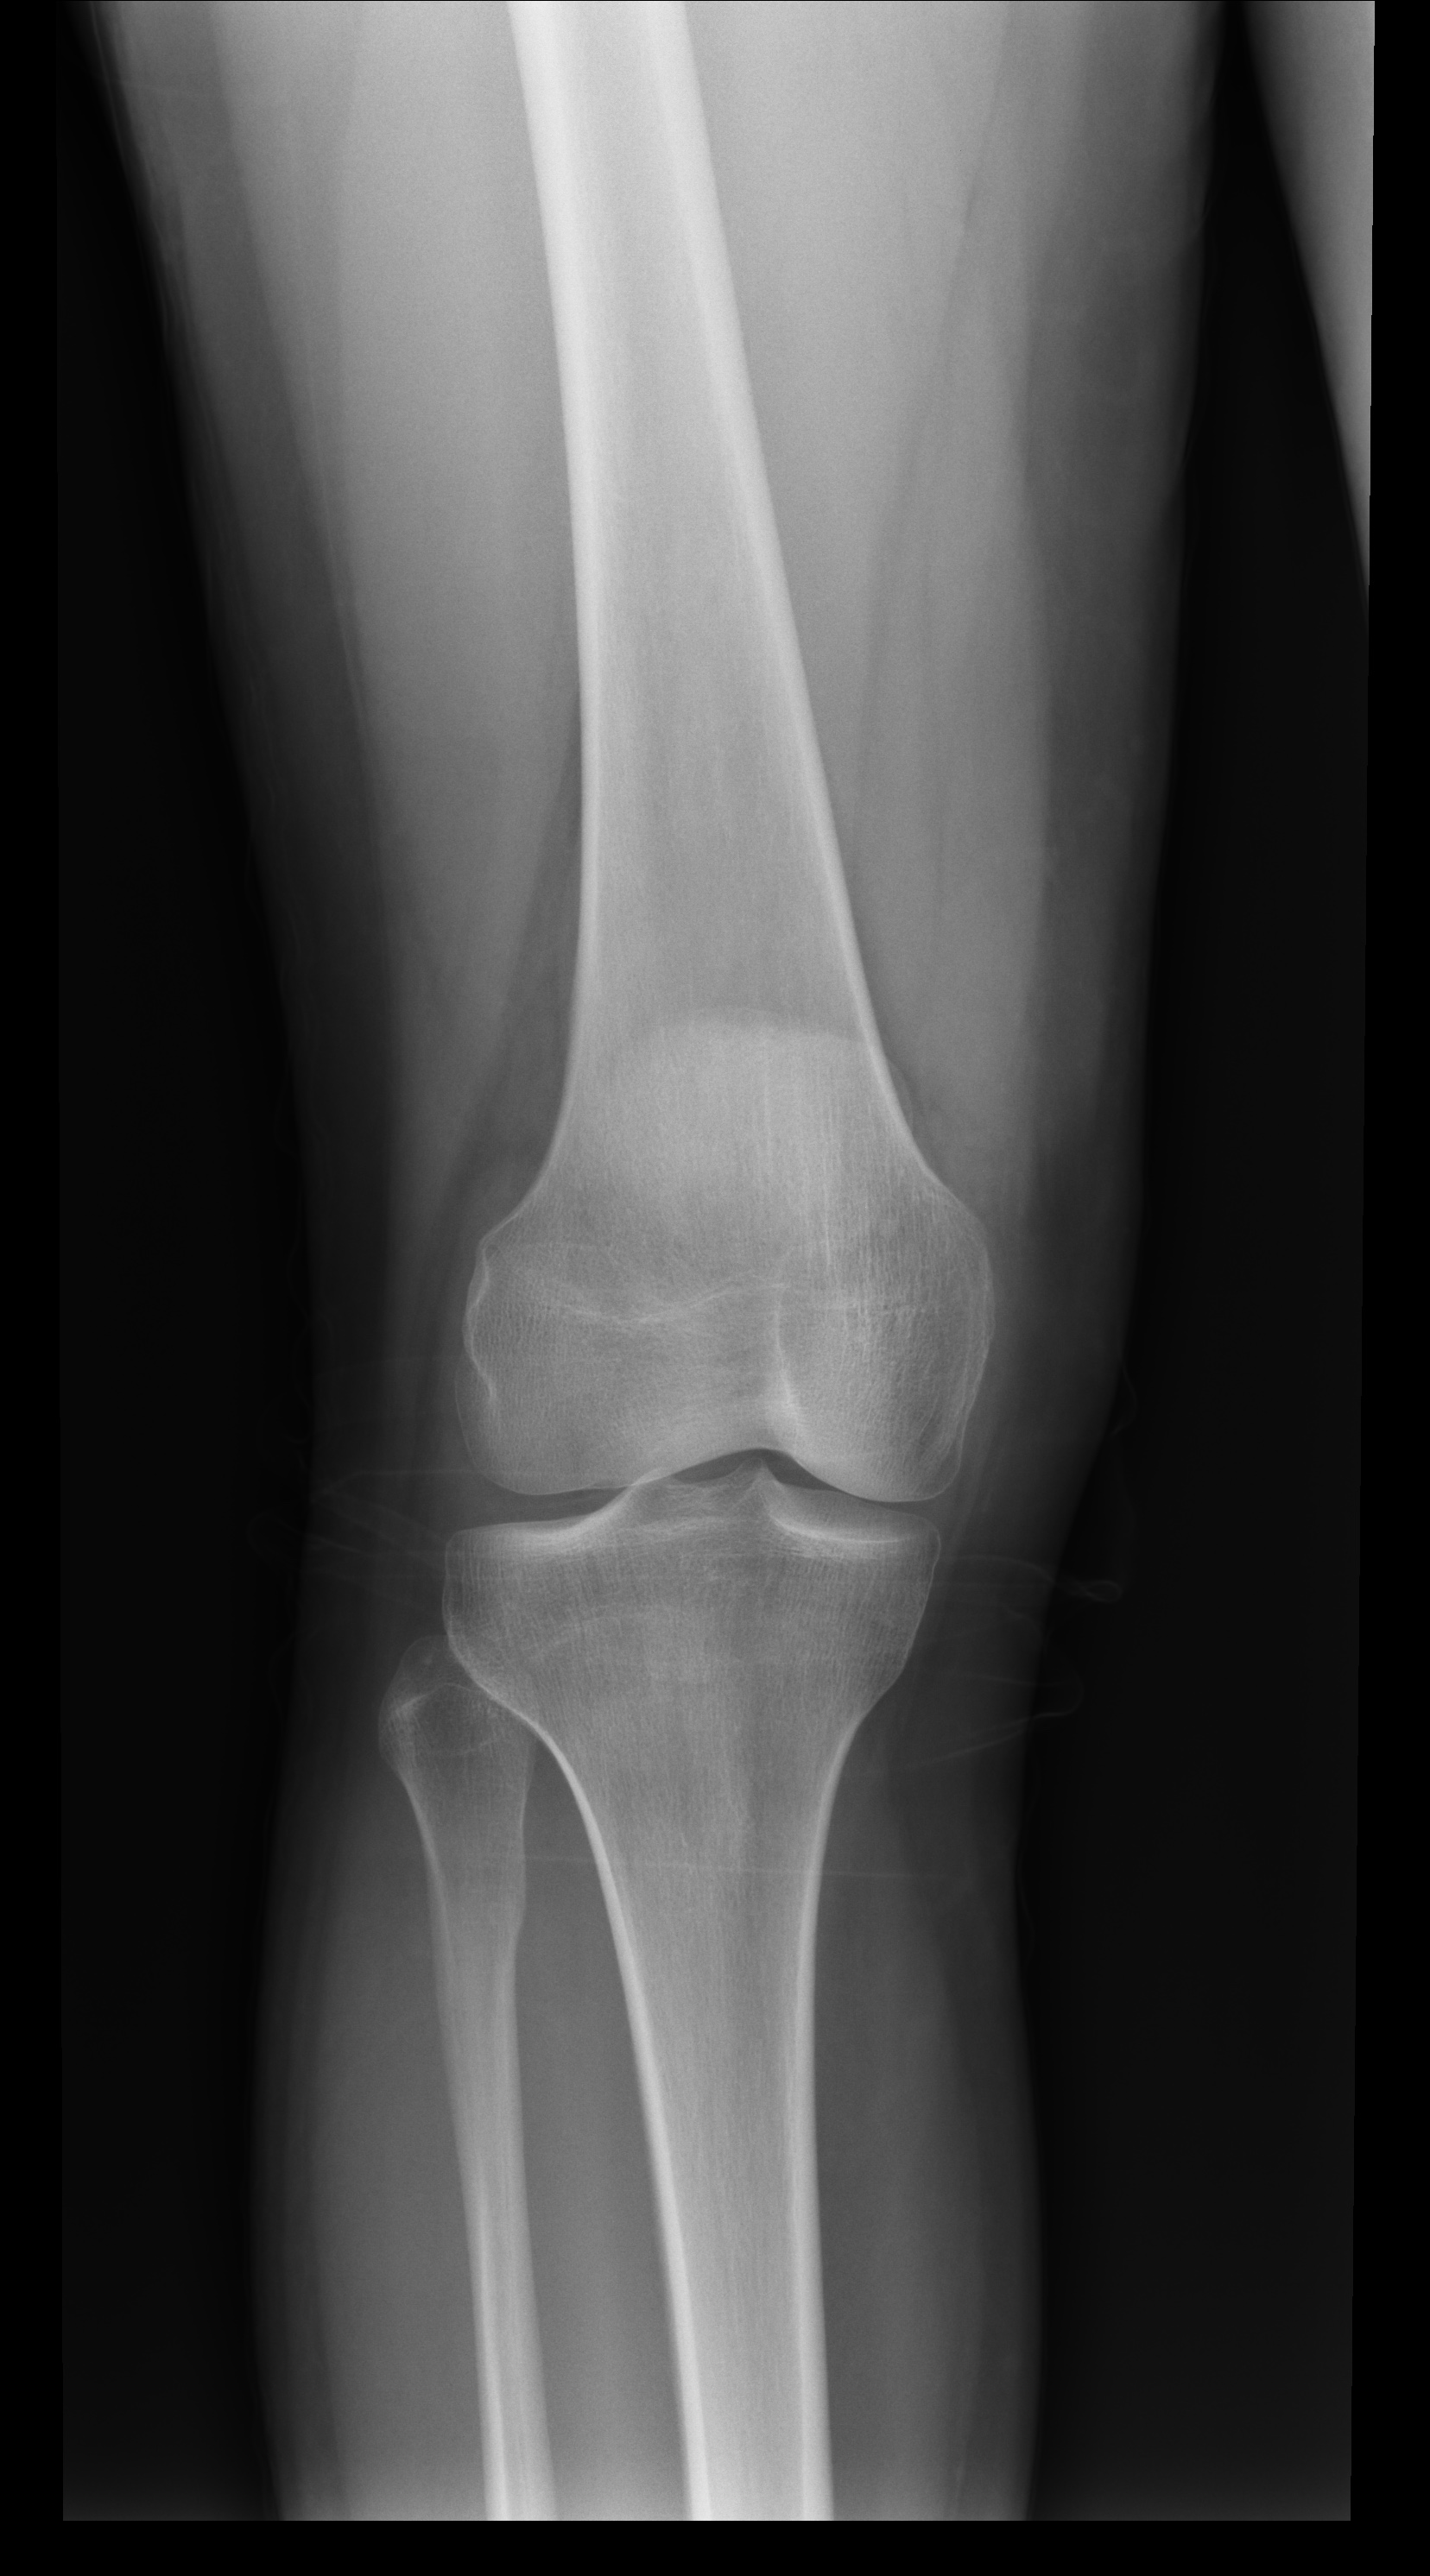

Paciente jóven que sufre un traumatismo al golpearse en la rodilla con el marco de una puerta, lo cual le impide mantener el peso sobre el miembro inferior derecho.

defecto de osificación del tubérculo tibial. No debemos confundir con rotura.